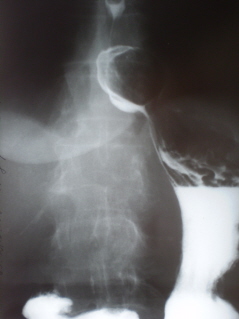

Протокол рентгенологического исследования. Со стороны органов грудной полости патологических изменений не выявлено. Глотка, пищевод и кардия свободно проходимы. Пищевод обычного расположения, формы и размеров, контуры его ровные, четкие. Желудок обычного расположения, формы и размеров. При натуживании, пальпации за экраном и в положении Тренделенбурга фиксируется пролабирование части желудка (иллюстрация 1) в грудную полость. При переводе пациентки в вертикальное положение грыжа пищеводного отверстия диафрагмы «самостоятельно вправляется».

Заключение (выводы):  Функциональная недостаточность пищеводного отверстия диафрагмы, скользящая (не фиксированная) грыжа пищеводного отверстия диафрагмы с пролабированием части желудка в грудную полость.